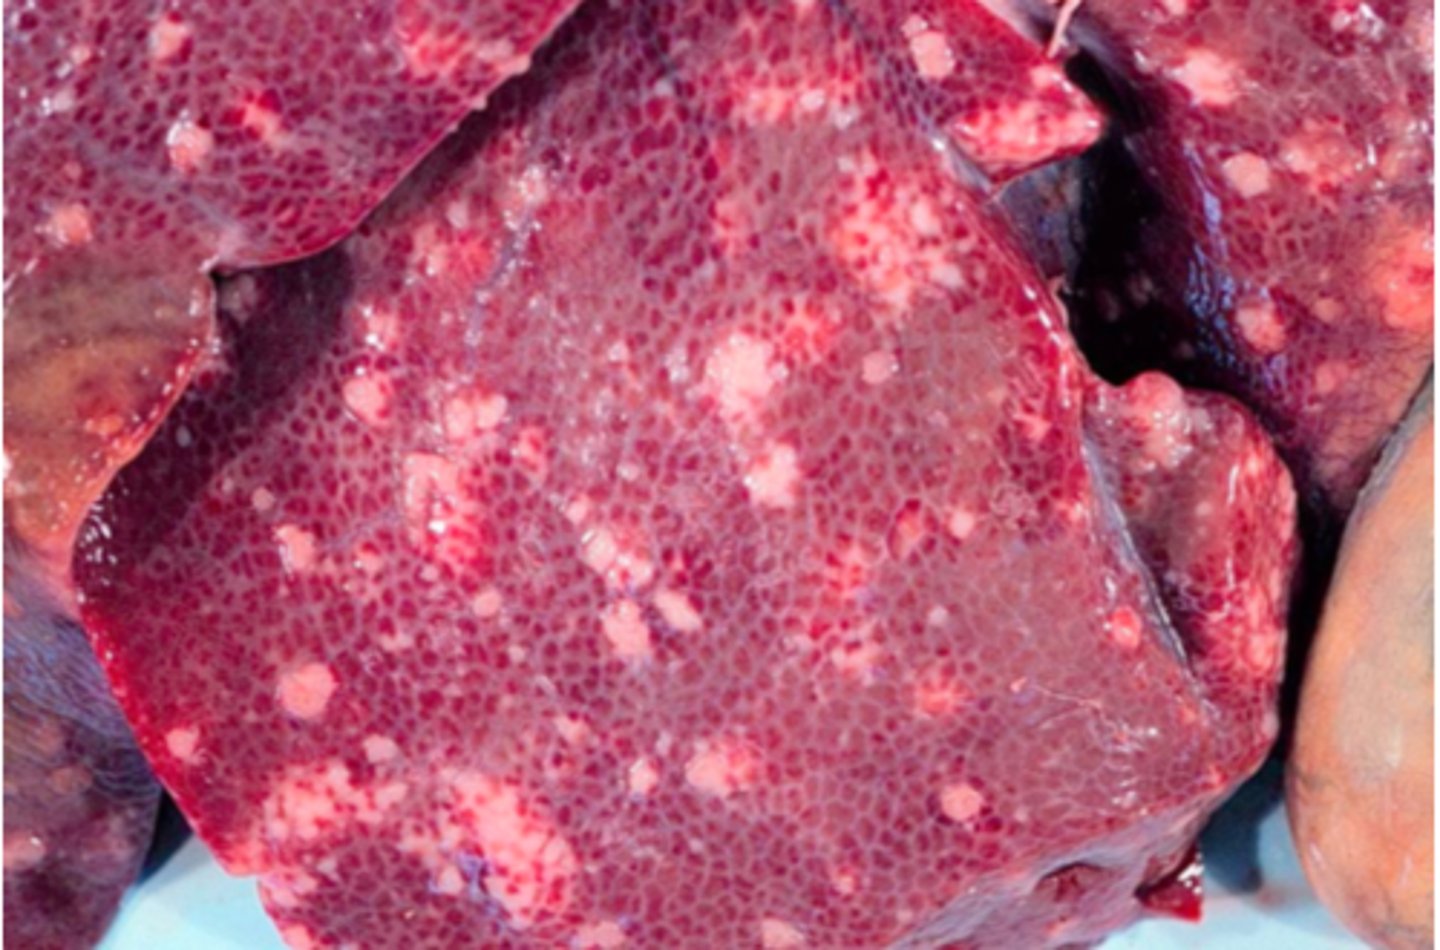

Akut, hæmorrhagisk og nekrotiserende hepatitis.

Ætiologi: infektion med Fasciola heptatica

Lever fra får, hvad er den patoanatomiske diagnose og ætiologien?

Kronisk multifokal, fibrøs, interstitiel hepatitis

Ætiologi: migration af Ascaris suum larver

Lever fra svin, hvad er den patoanatomiske diagnose og ætiologien?